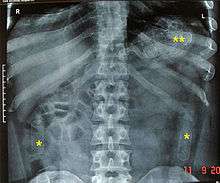

The cavity search has proven ineffective in the prevention of smuggling objects as it cannot detect objects in the intestines or stomach. It has become normal for authorities to isolate individuals in a monitored environment until they pass excreta and/or to x-ray the individual as it is less invasive and psychologically damaging.

Some inmates and human rights activists argue that body cavity searches are done not so much to stop the flow of contraband but rather to harass and humiliate detainees. A visual inspection of the rectum will not reveal objects concealed deeply inside. Likewise, it is possible to circumvent detection during manual body cavity searches. In some instances, suspects swallow packages of drugs protected by condoms and allow them to pass through their digestive tract. Only diagnostic imaging will reveal the concealed contraband.